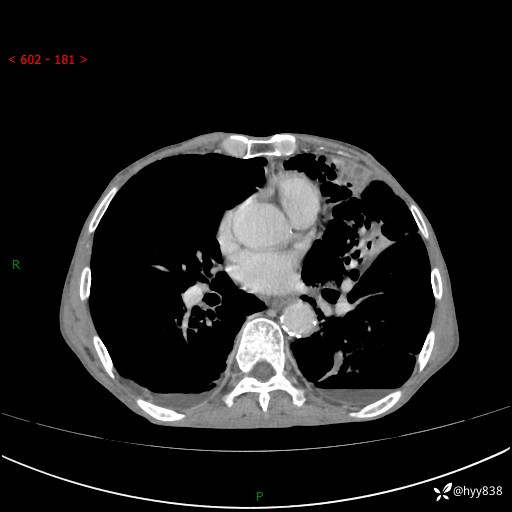

胸部CT平扫+增强